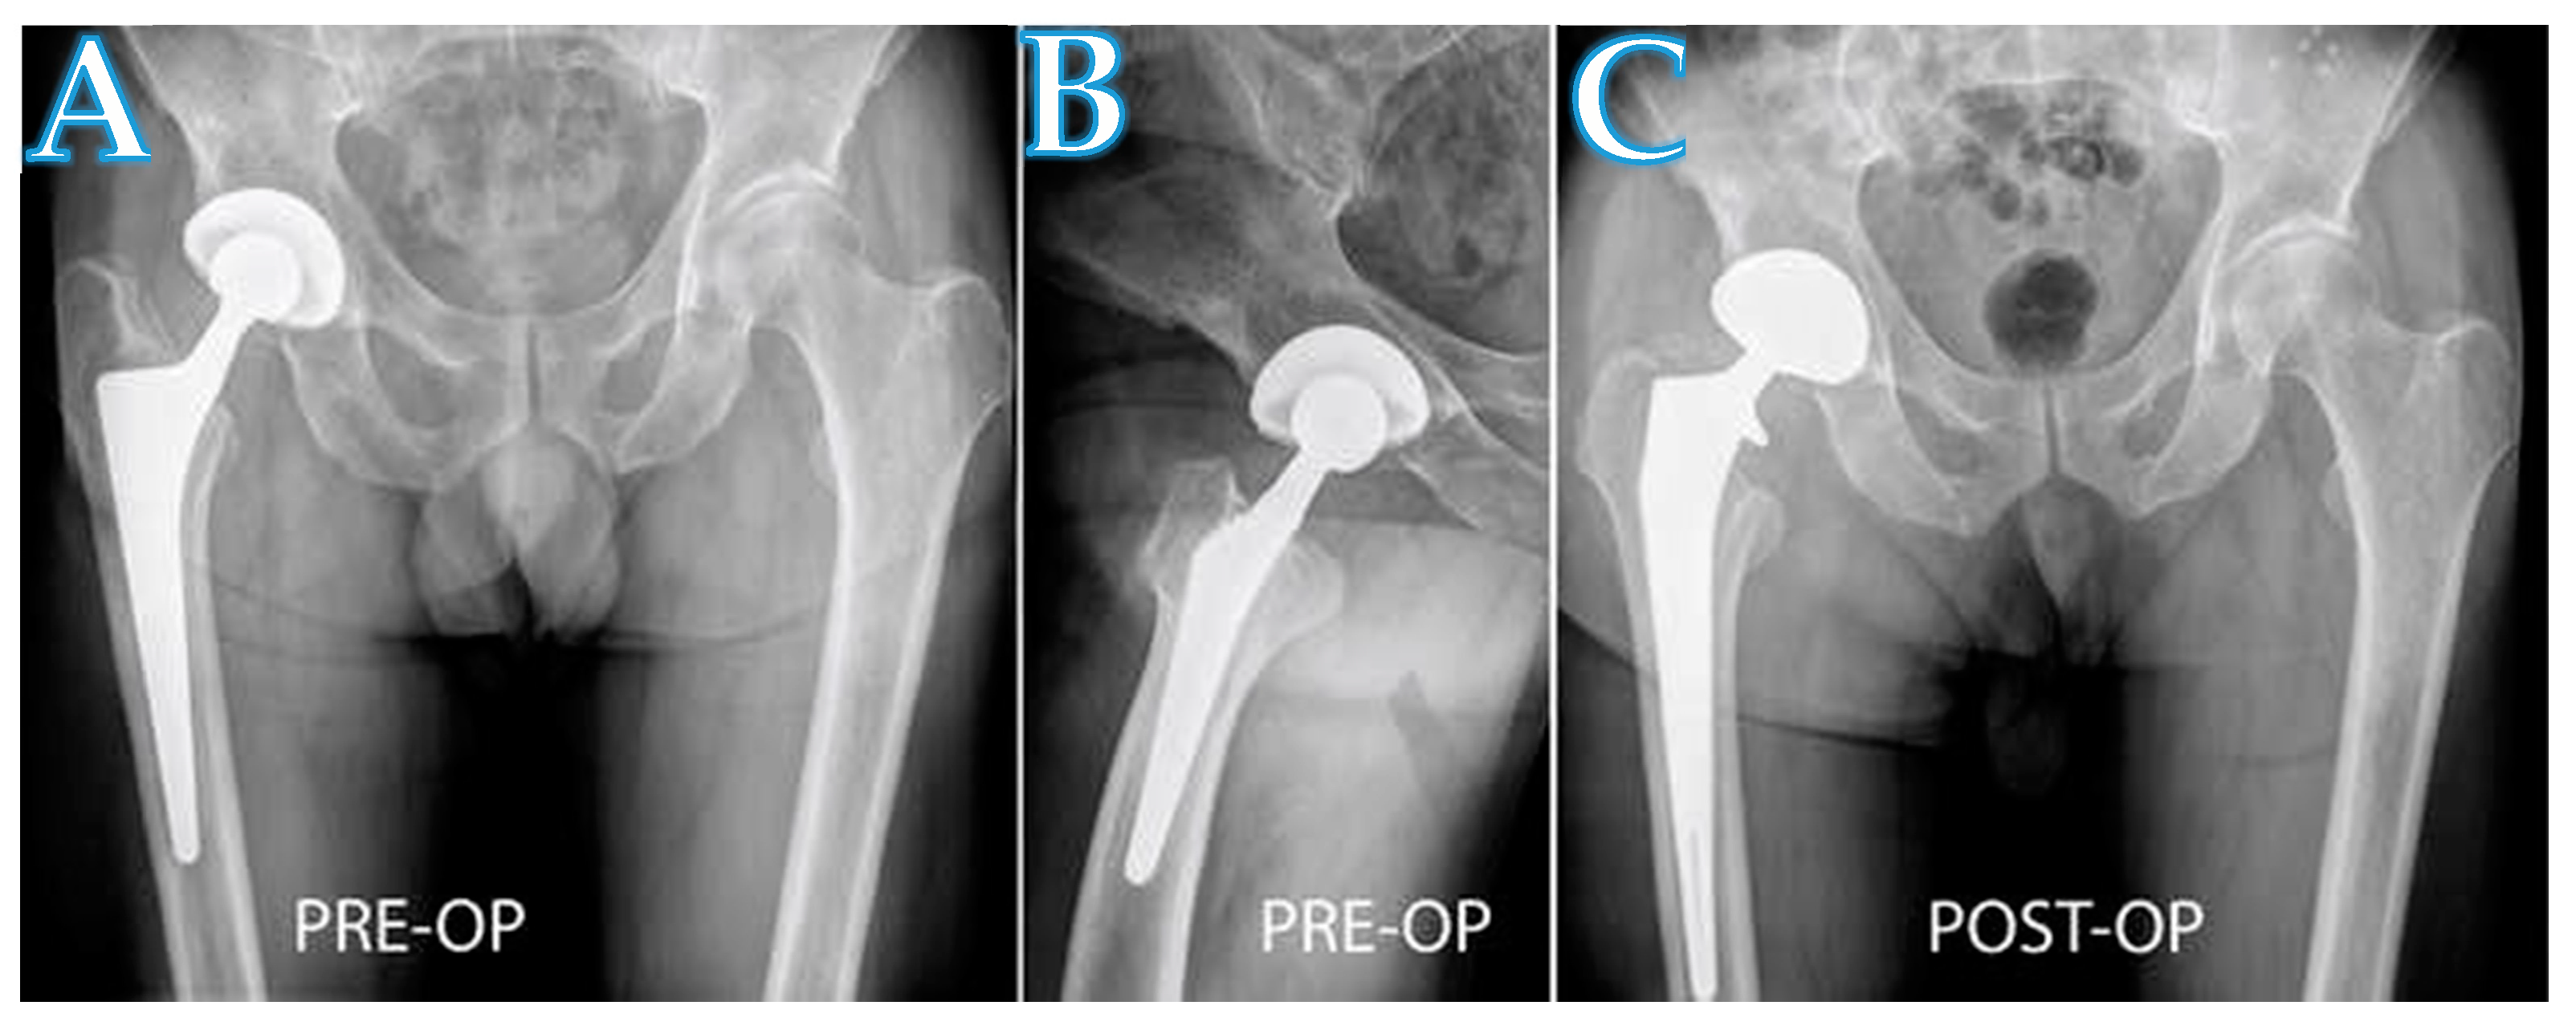

Figure 4.

A radiograph showing a patient with aseptic loosening of a femoral stem in the right hip (A,B). The implantation of the long revision stem was performed with a proximal extension of the DAA (C).